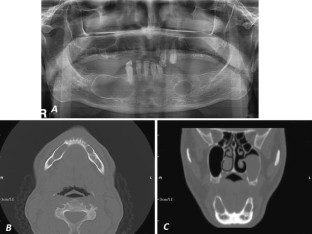

Glandular odontogenic cysts (GOCs) of the jaw are rare with well-defined limits radiologically, unusual histopathological features and a high recurrence rate. The radiographic appearance of GOCs vary and are not pathognomonic. Definitive diagnosis of the GOC is established only by histopathological examinations. Histologically, GOC is characterized by a thin nonkeratinized squamous epithelial lining, with papillary projections, nodular thickenings, mucous (goblet) cells with intraepithelial mucous pools and intraepithelial glandular, microcystic or duct-like structures. We present an unusual case of a bilateral GOC in the mandible. This case report is also the first documented case of bilateral GOC in the mandible.

Fig. 1